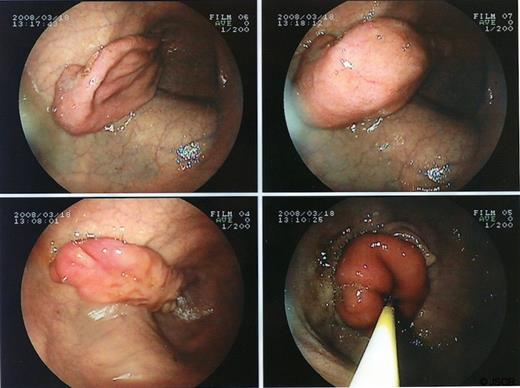

An upper gastrointestinal endoscopy showed a inverted intraduodenal diverticulum like a “giant pseudo-polip” that insufflated and deinsufflated spontaneously (figure 2).

Upper intestinal endoscopy showing the inverted intraduodenal diverticulum